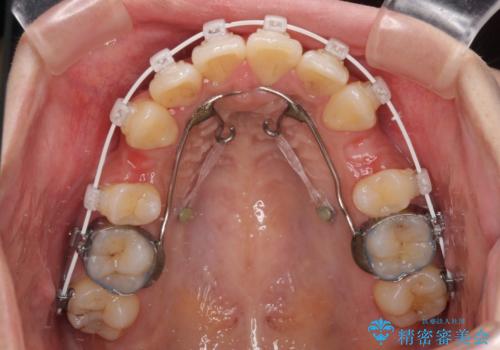

- 審美装置

アンカースクリューと補助装置を使用して上顎大臼歯を遠心移動させることで咬み合わせを改善し、更には口元の突出感を改善するために上下左右の小臼歯4本を抜歯し、ワイヤー装置によりデコボコを解消しながら口元の突出感も改善していくこととしました。